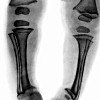

Рентгенография трубчатых костей ребенку

Рентгенография трубчатых костей ребенка может быть использована для диагностики рахита, хондродистрофии, несовершенного остеогенеза, трещин и переломов, опухолей костей, раннего врожденного сифилиса, остеомиелита, туберкулеза костно-суставного сустава, определения «возраста кости» Основными анализируемыми параметрами являются форма и размер кости или ее отделов, контуры кости, состояние структуры костной ткани, анатомические взаимоотношения в суставах, состояние зон роста и соответствие возраста кости. до фактического возраста детской астмы. Поскольку для определенного числа заболеваний существует так называемый рентгенологический период, когда патологические изменения на рентгенограммах еще не обнаружены, рекомендуется рентгенологическое исследование трубчатых костей ребенка в дополнение к КТ или МРТ.